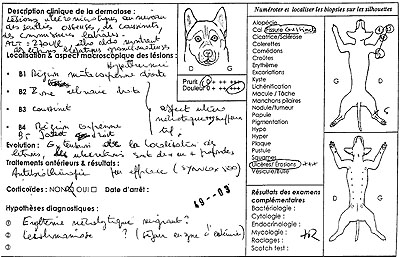

Commémoratifs

Un chien croisé (Labrador X Setter), mâle castré de 10 ans, présente une dermatite ulcéro-nécrotique, douloureuse, non prurigineuse, extensive, intéressant les points de pression des membres, les commissures labiales et les coussinets. On note des fissures cutanées sur les coussinets. Un bilan biochimique révèle une augmentation des ALAT et une échographie hépatique des lesions nodulaires du parenchyme hépatique. Le chien est hyperthermique.

Photo 1 : extrait de la feuille de commémoratifs

transmise avec les biopsies cutanées.

Hypothèses cliniques

- Érythème nécrolytique migrant

- Leishmaniose

Examens complémentaires

Cinq biopsies cutanées au trépan 6 mm de Ø sur le métacarpe droit, la pointe du coude droit, le carpe droit, le jarret droit, un coussinet de l’antérieur droit.